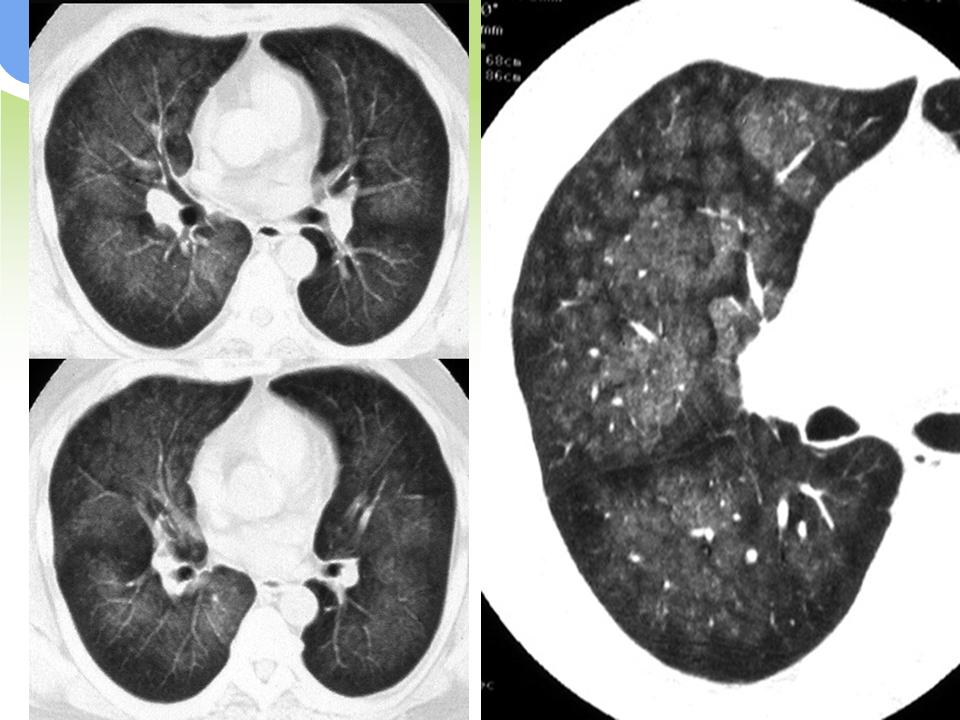

肺部病变的CT基本征象